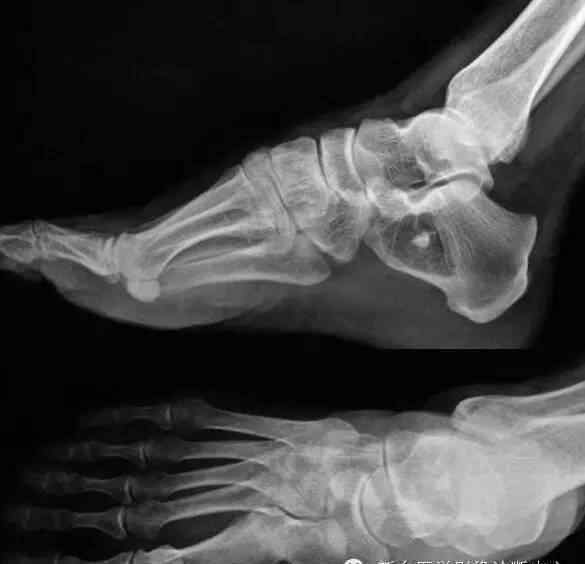

跟骨六处无法分辨的损伤。

结果:

1.跟骨骨髓窦

2.跟骨脂肪瘤

3.跟骨囊肿

4.跟骨动脉瘤样骨囊肿

5.跟骨骨髓窦

6.跟骨单眼巨细胞瘤